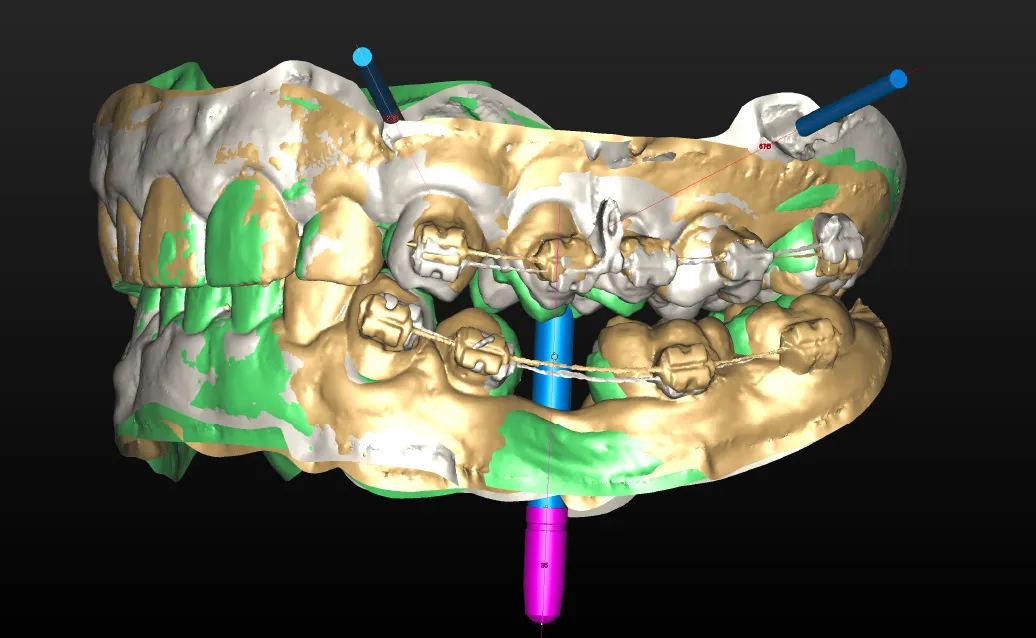

デジタルシミュレーション 院長によるご説明

患者様とご一緒に、デジタルシュミレーションを行います。患者様のお気持ちを反映した、納得のシュミレーションをご覧いただけます。

ビジュアル化された手術計画は、患者様も治療内容を理解し易く、納得感を持って治療をご決断いただけます。

いまだ多くの歯科医療機関が未対応な中、当院では2000年代より全患者様に無償で提供しています。

当院では、治療の正確性、安全性を高めるために、治療の難易度に関係なく全てのケースでサージカルガイドを無償でご用意し、手術に臨みます。